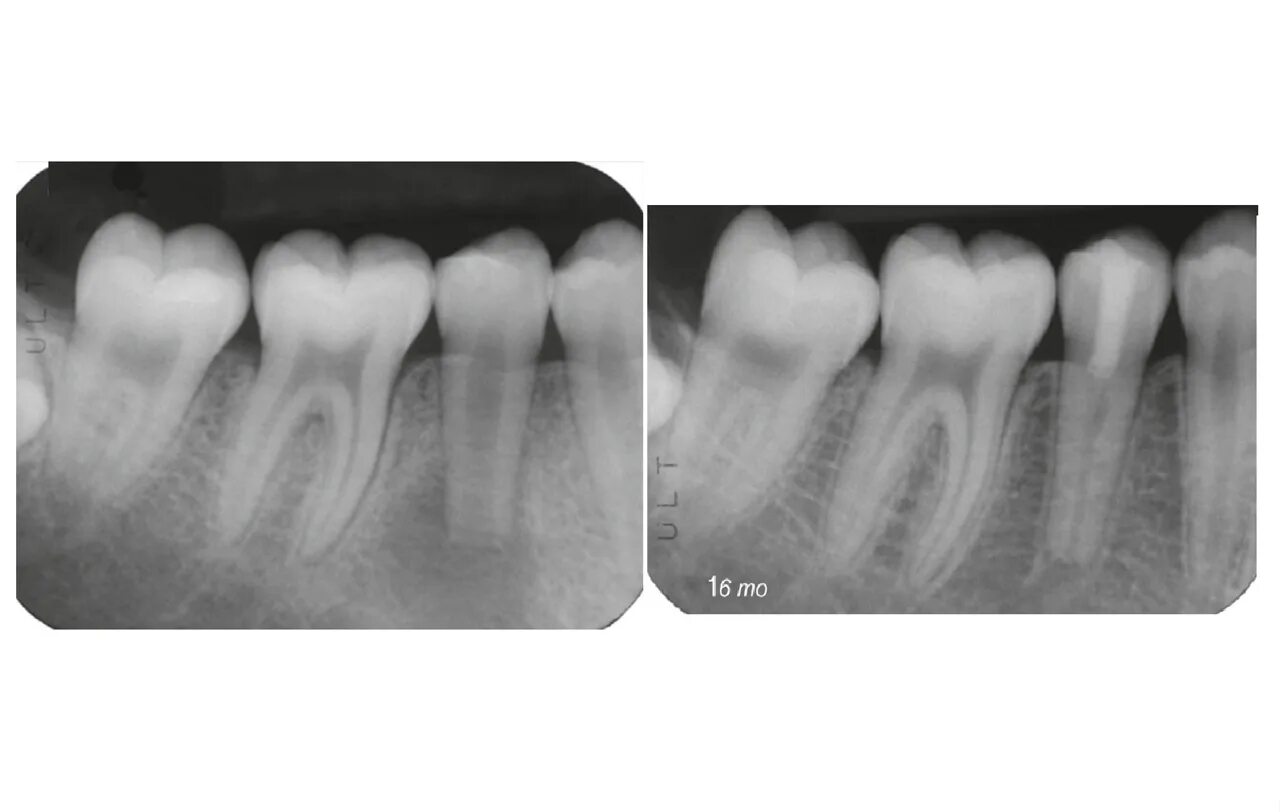

Лечение пульпита с несформированными